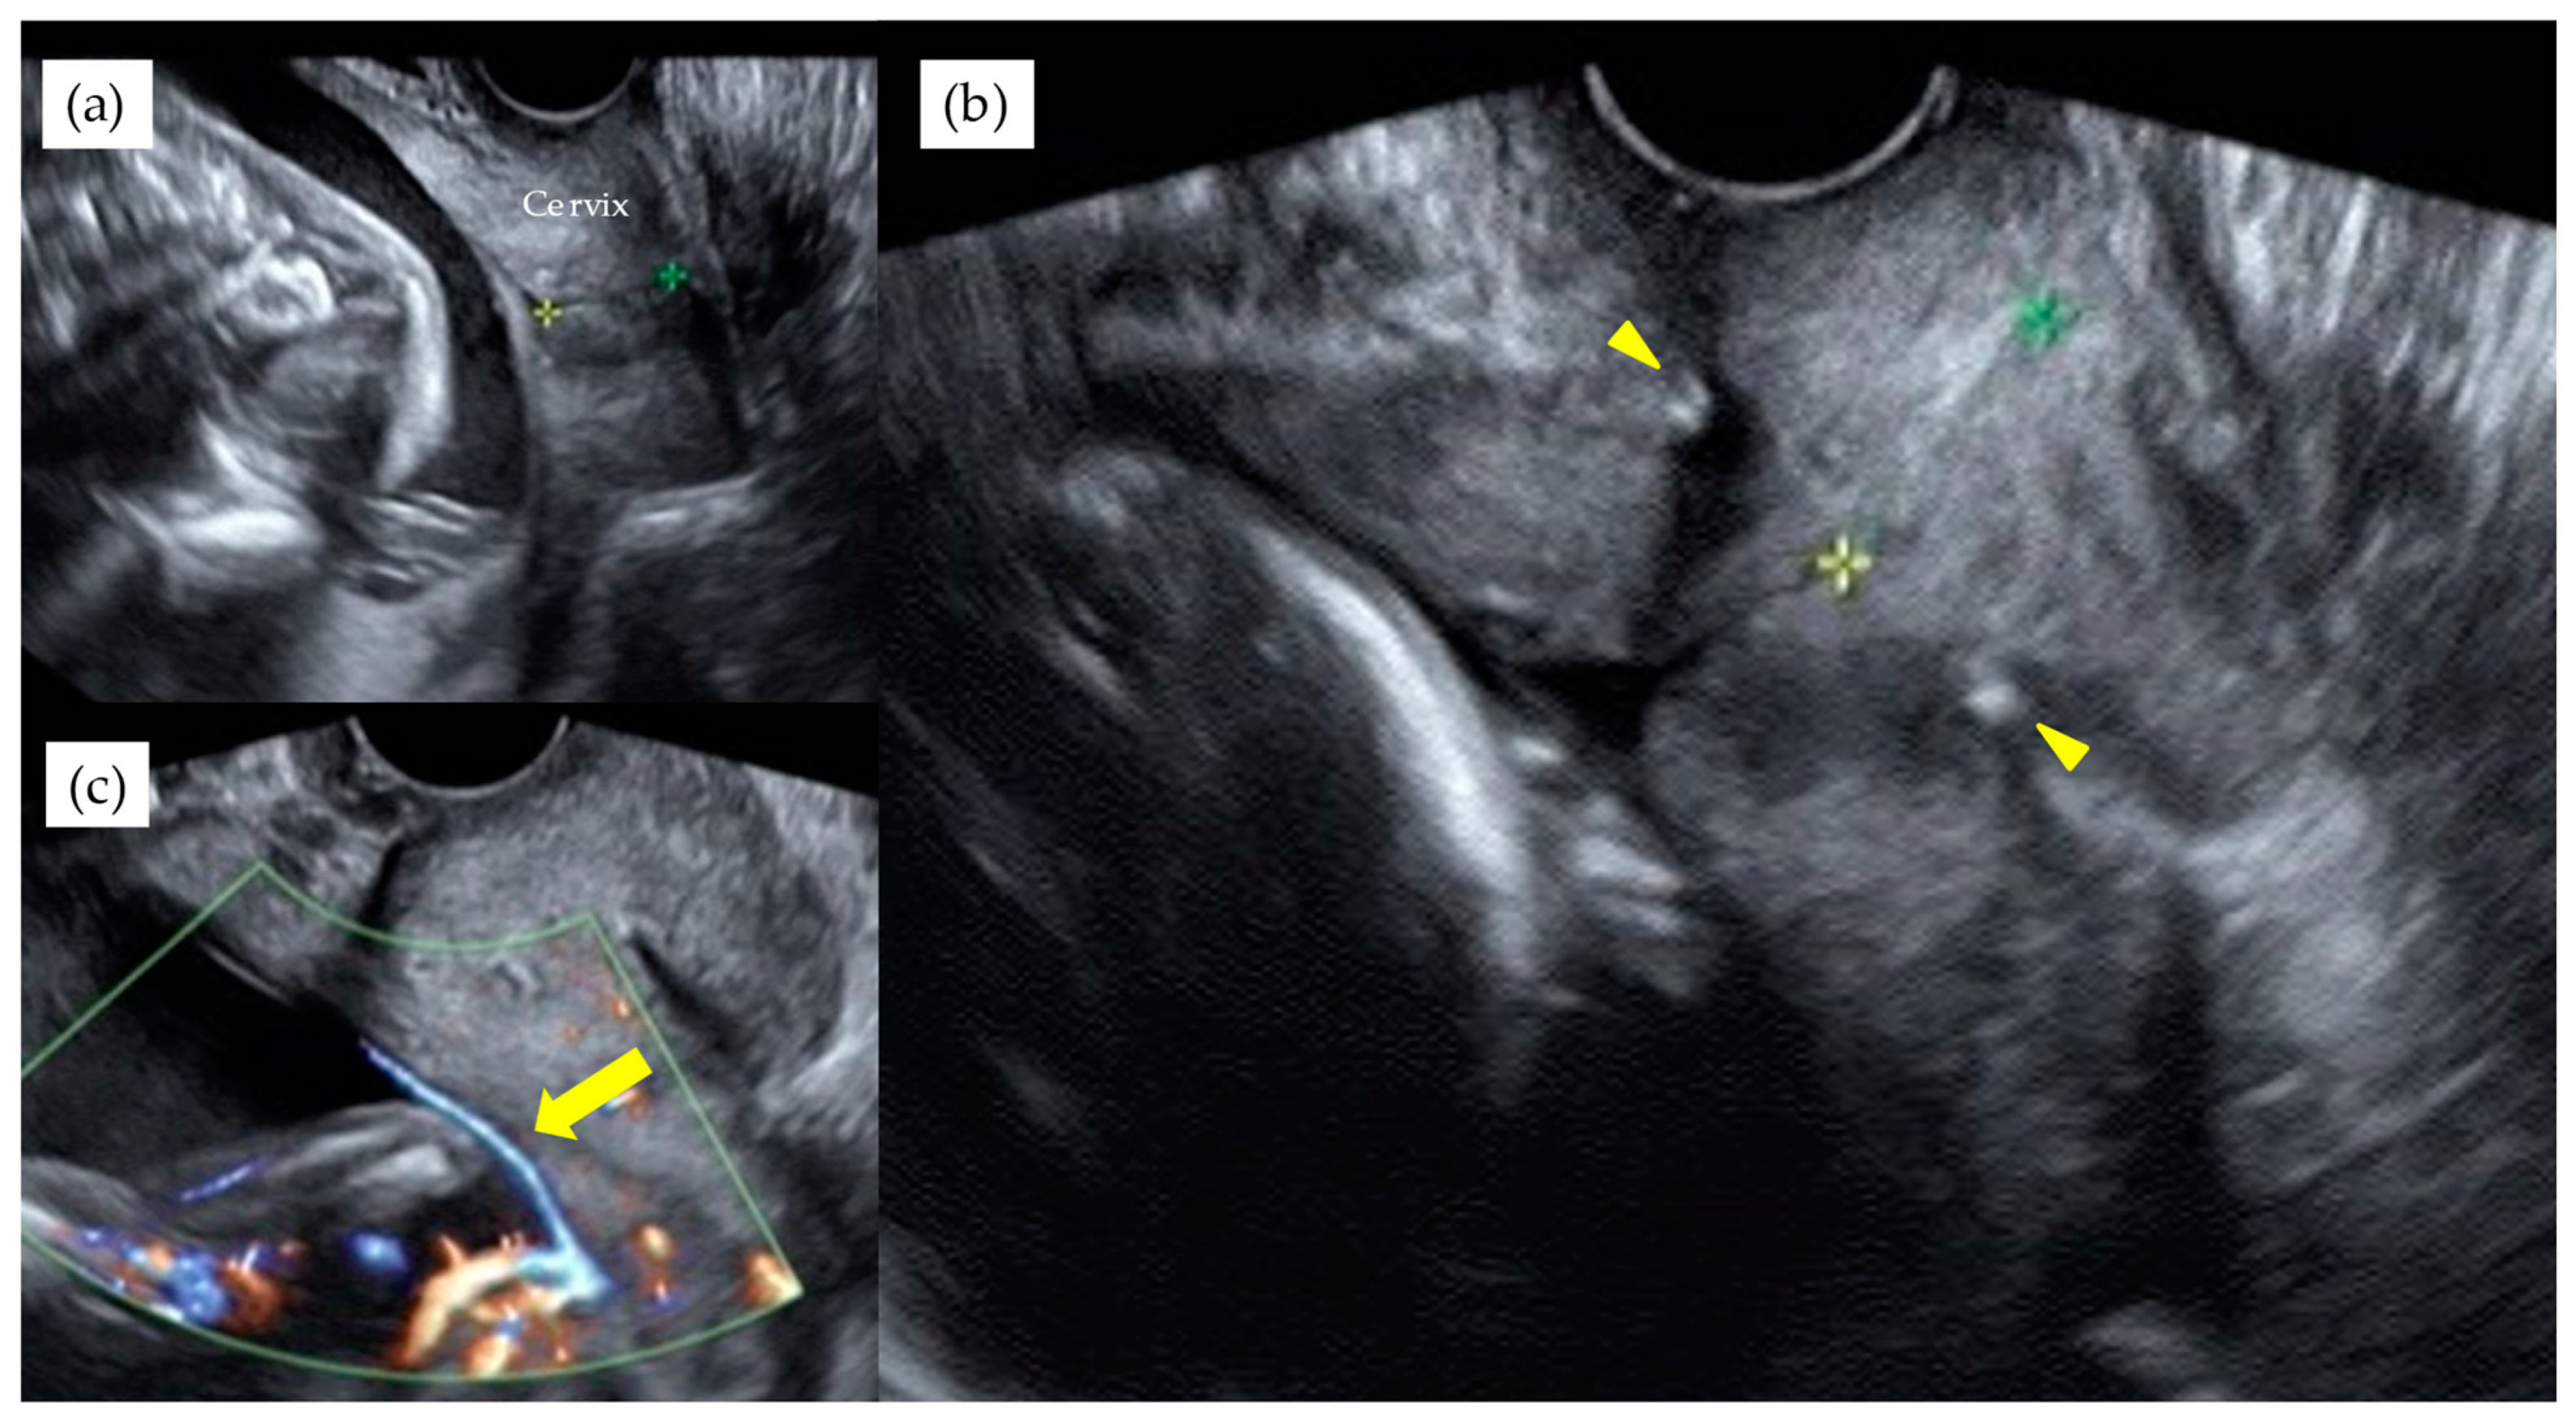

Table 3 shows the results of management and operative outcomes. In 31 cases (56.4%), including three twin pregnancies, tocolytic therapy was necessary (ritodrine hydrochloride and/or magnesium sulfate), and a steroid for fetal lung maturation was given in 9/13 cases (69.2%) delivered before the 34th GW. An abnormal fetal heart rate pattern without uterine contractions was detected in one case in the type 1 group, and this case exhibited a relatively thick artery near the internal ostium (Figure 2). Cervical cerclage via the McDonald technique was performed in two cases in the type 1 group. One of these cases was a singleton pregnancy at 20th GW and a cervical length of 2.1 cm, delivered by CS at 33rd GW. The other was a monochorionic-diamniotic pregnancy case at 20th GW and a cervical length of 1.7 cm, delivered by CS at 31st GW; this patient had a previous history of preterm singleton delivery at 34th GW. Blood flow of fetal vessels was confirmed post-cerclage in both cases (Figure 3). Resolution was observed in 12 cases (21.8%) in total. An emergent CS was performed in 25 cases with increased uterine contractions and in one case with an indication of hypertensive disorder of pregnancy; none of these cases experienced the premature rupture of membranes. Although the Ward technique was more frequently used in the non-type 1 group, the details as to operative outcome showed no significant difference between the two groups. The transection of the placenta to approach the fetus was not used in any of the cases. All cases underwent a cesarean section, even in those cases of resolution of VP.

Figure 3. A monochorionic diamniotic pregnancy case of type 1 VP, with previous history of preterm singleton delivery at 34th GW, showed cervical length of 1.7 cm at 20th GW (a). Blood flow of fetal vessels were confirmed after cervical cerclage performed. Arrowheads indicate string of cervical cerclage (b). Arrows indicate vasa previa with color Doppler image after cervical cerclage (c). This patient delivered by CS at 31st GW. The yellow and green stars indicate the cervical length.